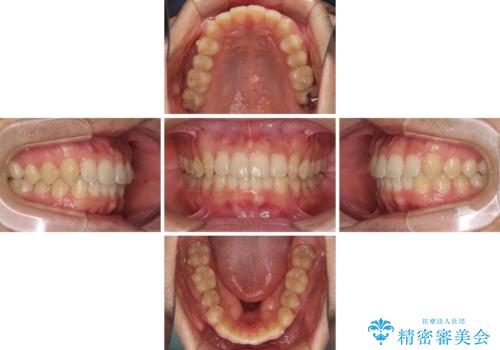

- 上下前歯のデコボコと深い咬み合わせを気にして来院された患者様です。

インビザラインによる上下歯列の拡大と、IPR(歯と歯の間を削る)にるスペースの獲得により、前歯のデコボコとディープバイトを改善することとしました。

もう少し下の前歯を整えたかったのですが、患者様の治療を早く終了させたいという希望により、細かい叢生を残しての終了となりました。